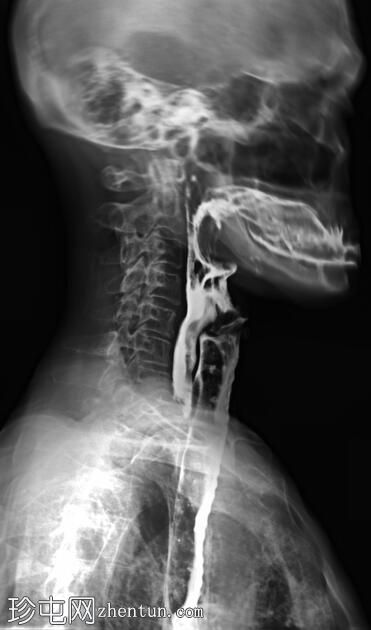

侧位

正位和侧位图像显示造影剂在咽部积聚,并伴有钡剂误吸至气道和支气管树。未见

肺

实变。

此外,胸椎存在退行性改变,表现为终板硬化和边缘骨赘形成。

透视图像显示钡剂误吸覆盖喉部和气管支气管树。